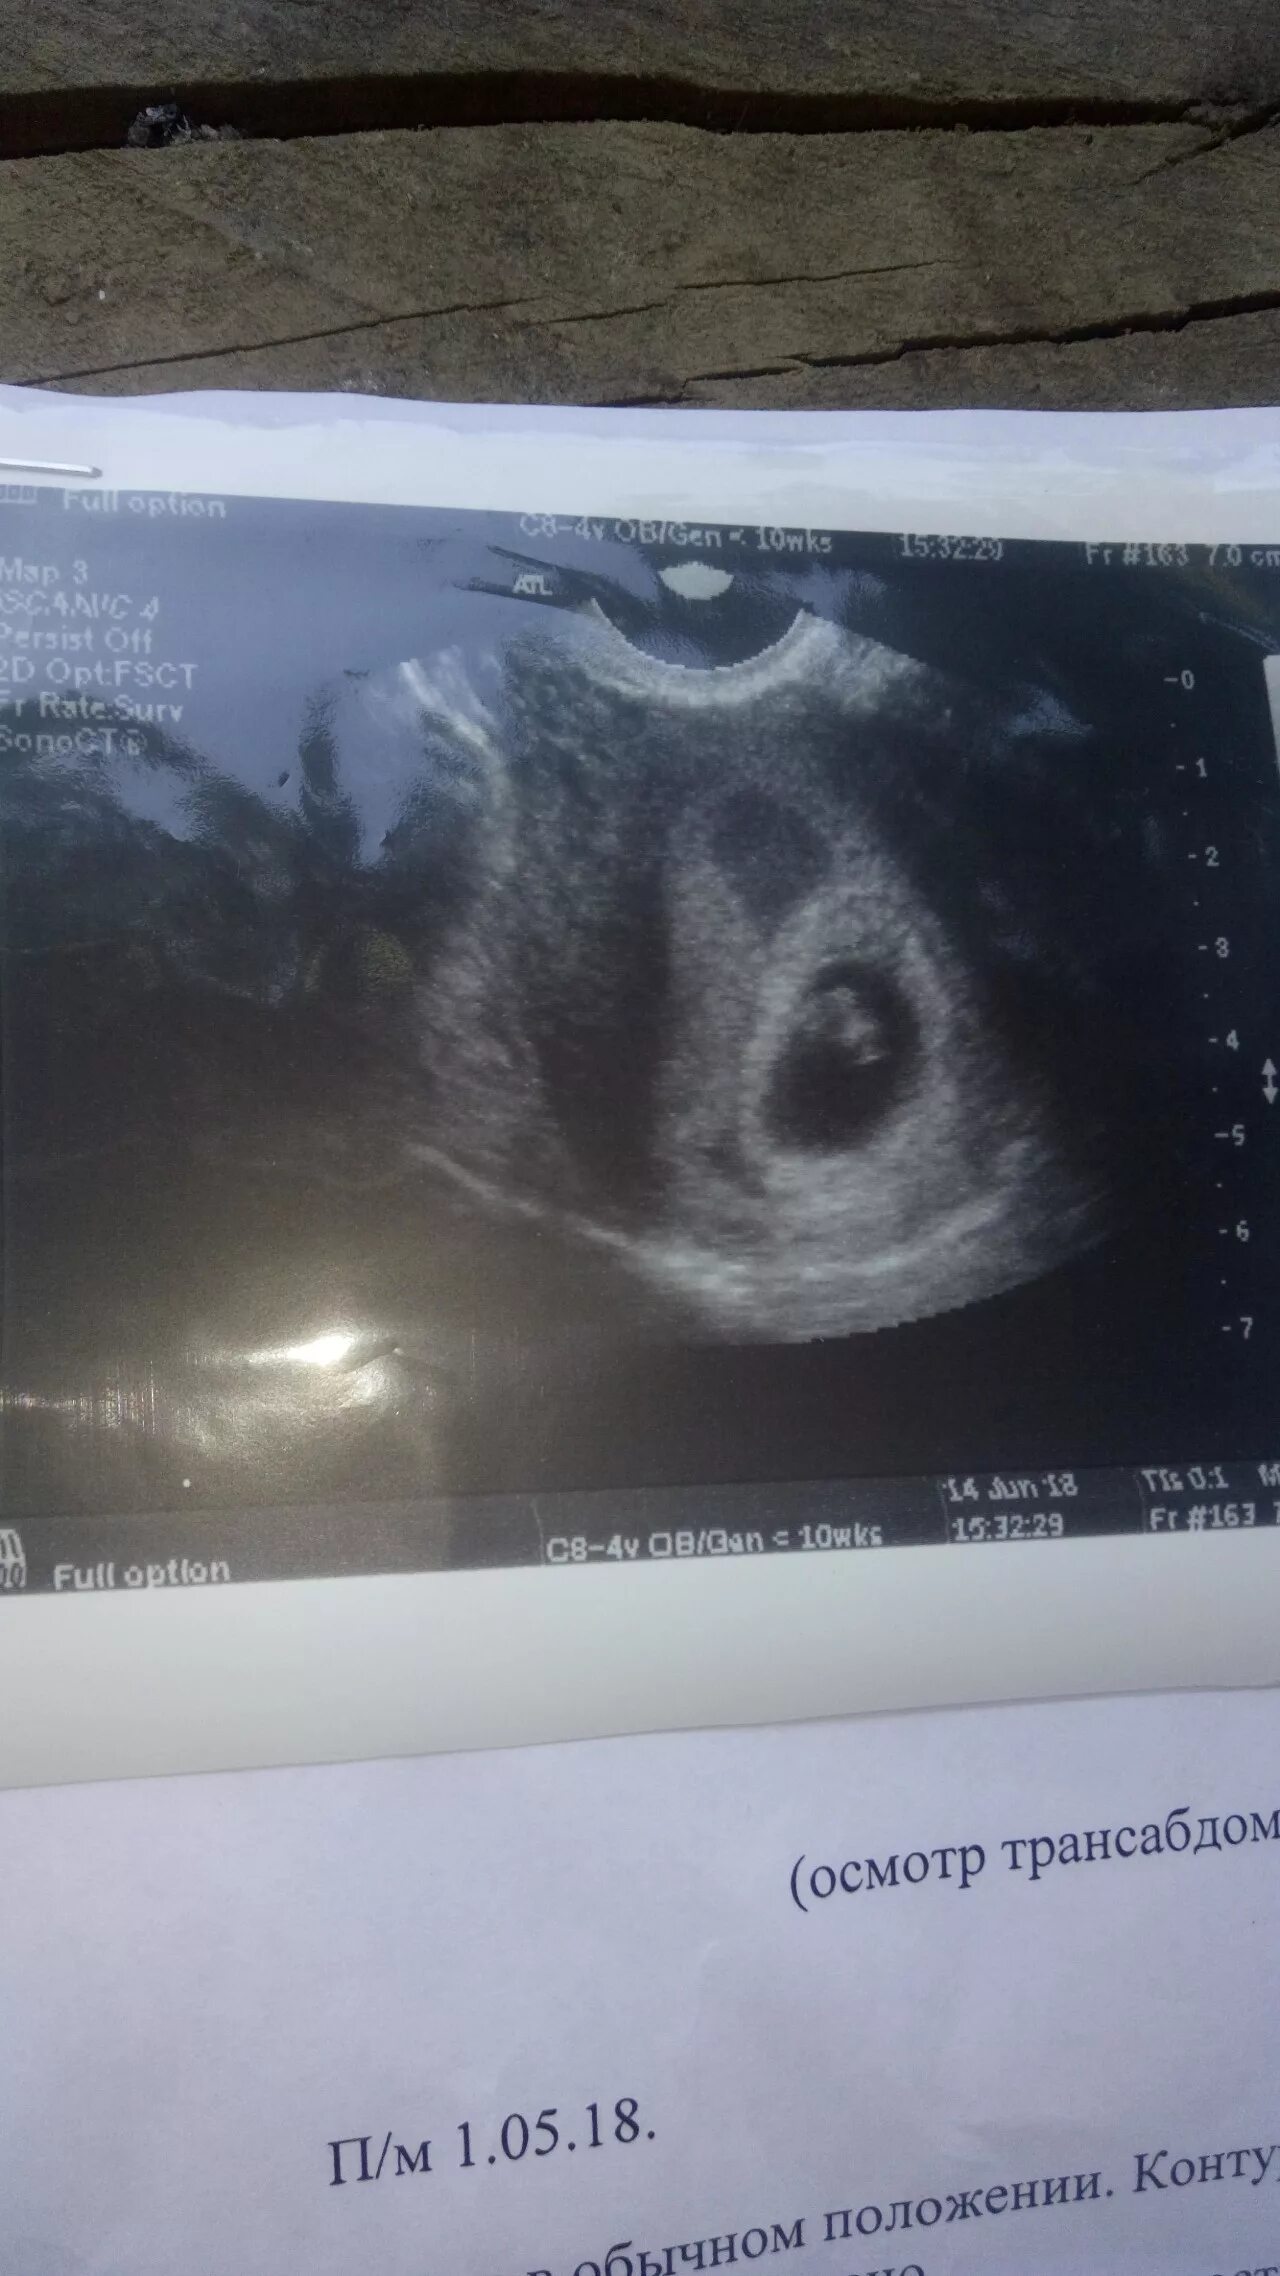

Вышла гематома форум